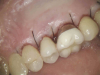

(3.) The initial surgical exposure revealed defects coronal to the crestal bone that were filled with granulation tissue and consistent with ECR.

Figure 3